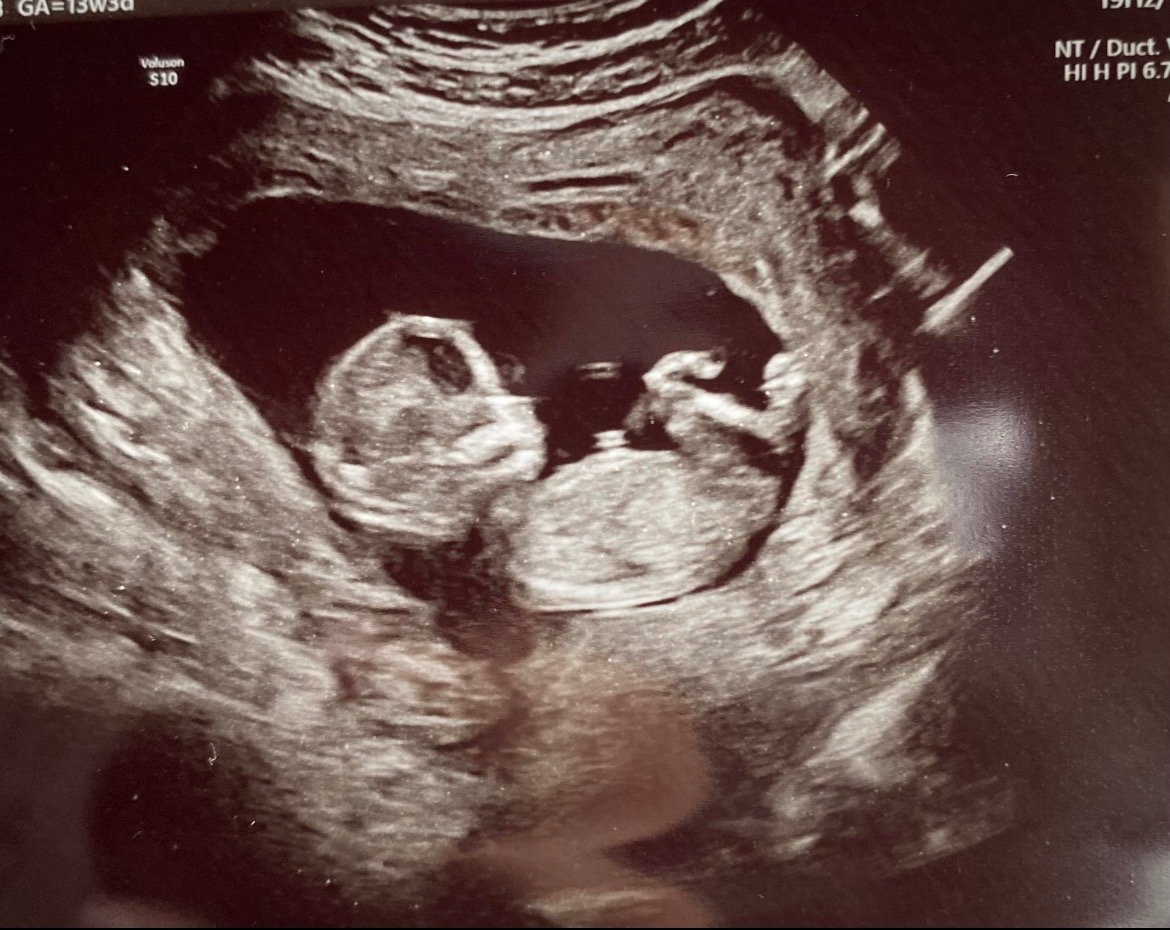

I’m reaching out as a very hopeful and loving soon to be Gigi. Destiny’s water broke early at 29 weeks, and she has been admitted to the hospital so she and baby boy can be closely monitored. The goal right now is for baby to keep growing until 34 weeks, when it will be safer to deliver him. Thankfully, they are both stable right now, and we are taking things one day at a time with faith and gratitude.

If you feel led to give, share, or pray for them, it would mean more than words can express. Most of all, we ask for continued prayers over this sweet baby boy, and that he continues to grow strong and healthy.